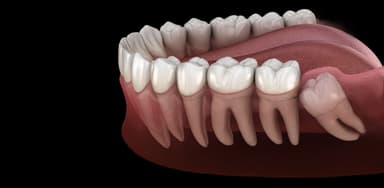

Nếu thực tế răng khôn sẽ không mọc lên hoàn toàn và đang có hai trường hợp xảy ra: di chuyển về hướng chân răng lân cận hoặc không bao giờ tiếp xúc với răng đối diện. Khi răng khôn cố gắng mọc lên, chúng di chuyển trong xương hàm. Nếu di chuyển theo hướng chân răng lân cận và gây áp lực lên răng này, sẽ gây tiêu chân răng. Điều này có thể làm hỏng vĩnh viễn răng lân cận và có thể phải thực hiện phẫu thuật hoặc nhổ răng lân cận. Ngoài ra, trong trường hợp răng khôn sẽ không tiếp xúc với răng đối diện, thì nó sẽ không có công dụng trong chức năng nhai và những rủi ro của việc giữ lại răng khôn này thường có thể vượt xa lợi ích của việc giữ nó. Ngược lại, nếu răng khôn mọc ngầm và không gây hại, thì tốt nhất là để nó ở vị trí hiện tại.

– Huỷ hoại xương và hàm răng: Nếu răng khôn mọc lệch và đâm vào răng bên cạnh, có thể gây hủy hoại răng đó, làm tiêu huỷ xương và cuối cùng dẫn đến việc phải nhổ răng. Triệu chứng thường bao gồm đau âm ỉ kéo dài ở khu vực này.

Răng khôn mọc lệch ngầm có thể gây tổn hại cho răng lân cận. Các túi xung quanh răng khôn tạo nơi lắng đọng các mảng bám vi khuẩn, thức ăn và cao răng. Điều này dễ dẫn đến sự hình thành sâu tại chân răng, đặc biệt là răng lân cận (răng số 7). Nếu sâu răng phát triển rộng tại chân răng số 7, có thể buộc phải nhổ cả răng khôn và răng số 7. Điều này sẽ ảnh hưởng đến chức năng nhai do răng số 7 đóng vai trò quan trọng trong quá trình ăn nhai.